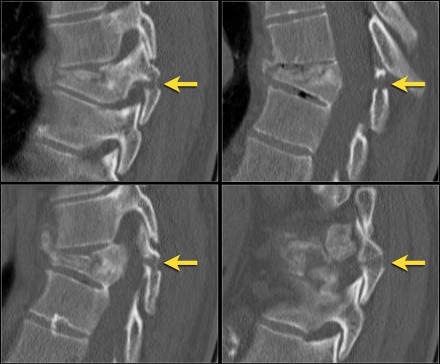

Sagittal fracture of vertebral body and posterior element

A sagittal fracture of the vertebral body and a sagittal posterior element fracture is seen in respectively 90% and 85% of cases of burst fracture cases.

Here are four examples.

In the Denis classification this would be a three column fracture -anterior/middle/posterior - indicating a very unstable fracture.

In the TLICS classification however this is a burst fracture, i.e. 2 points for morphology.

The treatment will depend on the PLC integrity and the neurological status.